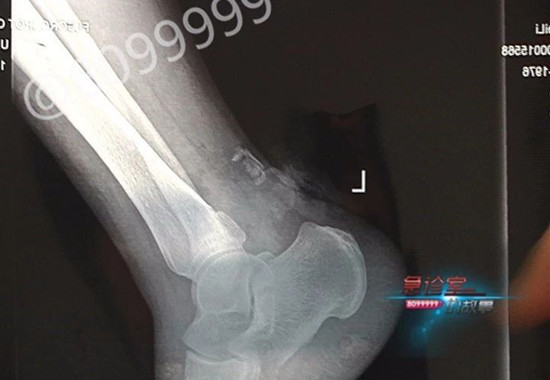

前不久,邱大姐骑着电动车下班回家时,在新螺丝湾附近遭遇飞来横祸,由于她当时是逆行,被迎面而来的一辆电动车撞上。撞击瞬间,邱大姐的左脚脚腕后部立马被削去一大块,顿时血流如注。但由于是自己逆行在先,只能自行前往医院进行治疗。经检查,邱大姐左脚跟腱被撞断,已然失去了行动能力。

据云南省骨科医院 修复重建显微外科中心 曹学新医生介绍,跟腱是我们身体当中最粗的一根肌腱,它的功能也是非常重要的,它是管着我们的脚,走路时候非常重要的一个器官,如果说这个跟腱断了的话,我们的脚尖是抬不起来的,它始终是下垂的。

在入院以后,邱大姐首先进行了跟腱修复手术。而对于医生来说,跟腱修复相对较为简单,用结实的线缝合起来即可,但在跟腱修复以后,伤口处出现的肌肉坏死、跟腱裸露在外的情况就比较棘手了。